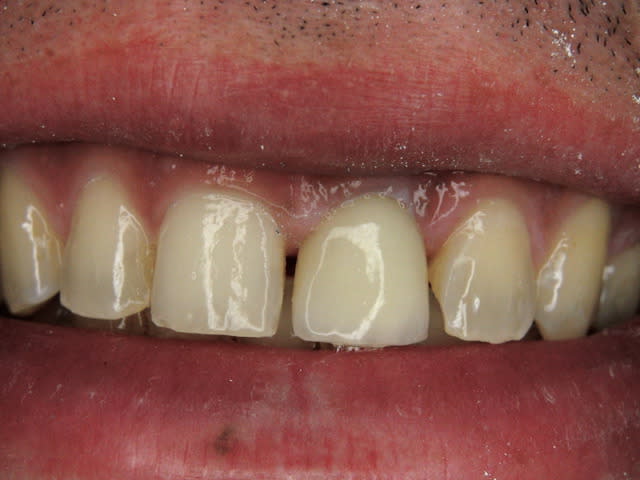

J'ai de tout en boutique..jeune homme 25 ans accident de piscine choc sur la bordure ( fêlure existante..fistule), extraction le jour même, temporisation 4 mois (avec un bout de trombone) Monobloc 16mm 60N, prep cap zircone droit 2/2 provisoire ion, temporisation 3 mois ceramo ceram..

J'ai de tout en boutique..jeune homme 25 ans accident de piscine choc sur la bordure ( fêlure existante..fistule), extraction le jour même, temporisation 4 mois (avec un bout de trombone) Monobloc 16mm 60N, prep cap zircone droit 2/2 provisoire ion, temporisation 3 mois ceramo ceram.. suite des photos :)